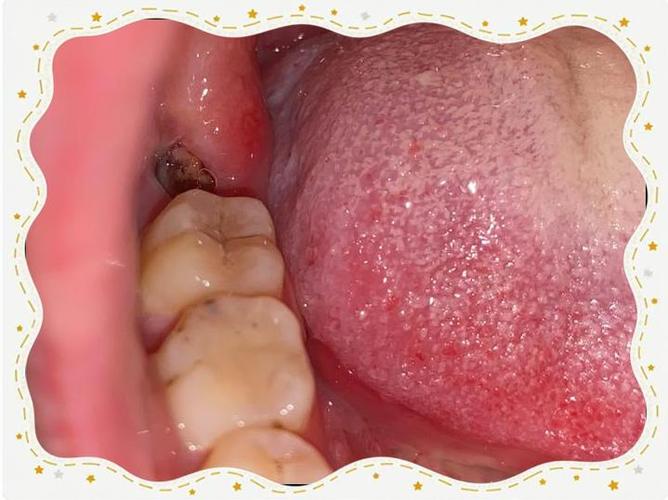

拔牙后,牙齿周围的牙槽骨会失去咀嚼力的刺激,逐渐发生“废用性萎缩”,这一过程在拔牙后的前3个月最为显著,骨吸收速度可达每月0.5-1mm;3个月后,骨吸收速度减缓,但持续至6-12个月,牙槽骨的高度和宽度会趋于稳定,形成相对致密、血供良好的“骨痂”,若在骨改建未完成时过早种植,可能导致种植体周围骨量不足,影响初期稳定性,甚至引发种植体松动、失败等问题。

等待一年,一方面让牙槽骨充分愈合,为种植体提供坚实的“土壤”;拔牙创口的软组织(牙龈、黏膜)也已完全恢复,避免术中或术后感染风险,若拔牙时伴有骨缺损(如根尖残留、感染等),一年时间 allows 身体彻底清除炎症病灶,骨再生更完全,为种植创造理想条件。